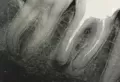

Мне около года назад удалили нервы в зубе (нижняя челюсть 6-й зуб). И этот зуб начал беспокоить, я сделала снимок и оказалось в одном из каналов этого зуба осталась часть инструмента которым непосредственно мне удаляли нервы. Я спрашивала у врачей и каждый по своему думает, одни говорят что не чего страшного нет от того что там часть осталась а другие рекомендуют срочно удалить. Не могли бы вы посмотреть снимок ( есть в электронном виде) и сказать свое мнение, очень нужен совет. Спасибо, буду ждать ответа

Если инструмент вышел за верхушку, то зуб придется удалить, так как в ближайшее время он у вас заболит и также возможен отек. Если инструмент просто в канале и доктор сможет обойти его и запломбировать канал, то ничего страшного.